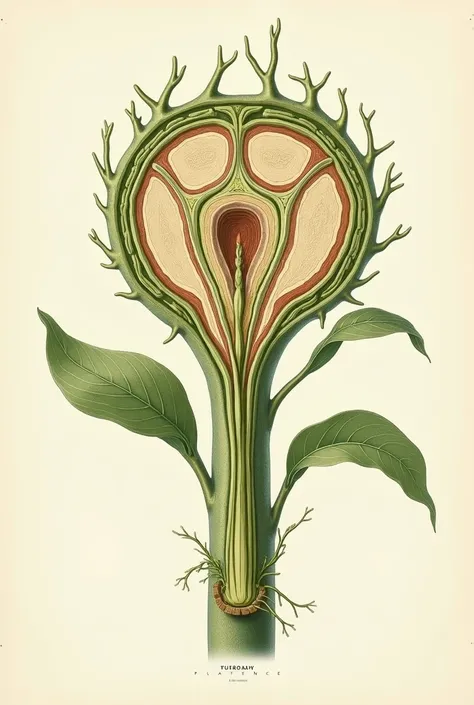

A diagram of the anatomy of the human body

Realice un dibujo de la piel. Coloque las siguientes referencias: Epidermis Fermis Hypodermis Keratinized squamous stratified epithelium Hair Sebaceous gland Sweat gland Pilo erector muscle Connective tissue Blood vessels Nerves Adipocytes

Epidermis Fermis Hypodermis Keratinized squamous stratified epithelium Hair Sebaceous gland Sweat gland Pilo erector muscle Connective tissue Blood vessels Nerves Adipocytes